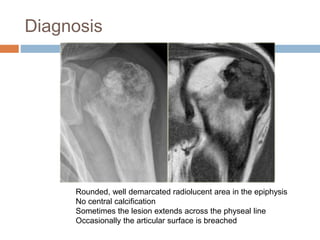

Diagnosis

Rounded, well demarcated radiolucent area in the epiphysis

No central calcification

Sometimes the lesion extends across the physeal line

Occasionally the articular surface is breached

Chondroblastoma

 Benign tumor of immature cartilage

 Occurs primarily in the epiphysis

 Usually proximal humerus, femur or tibia

 Age– around the end of growth period or in

early adult life

 Male predilection